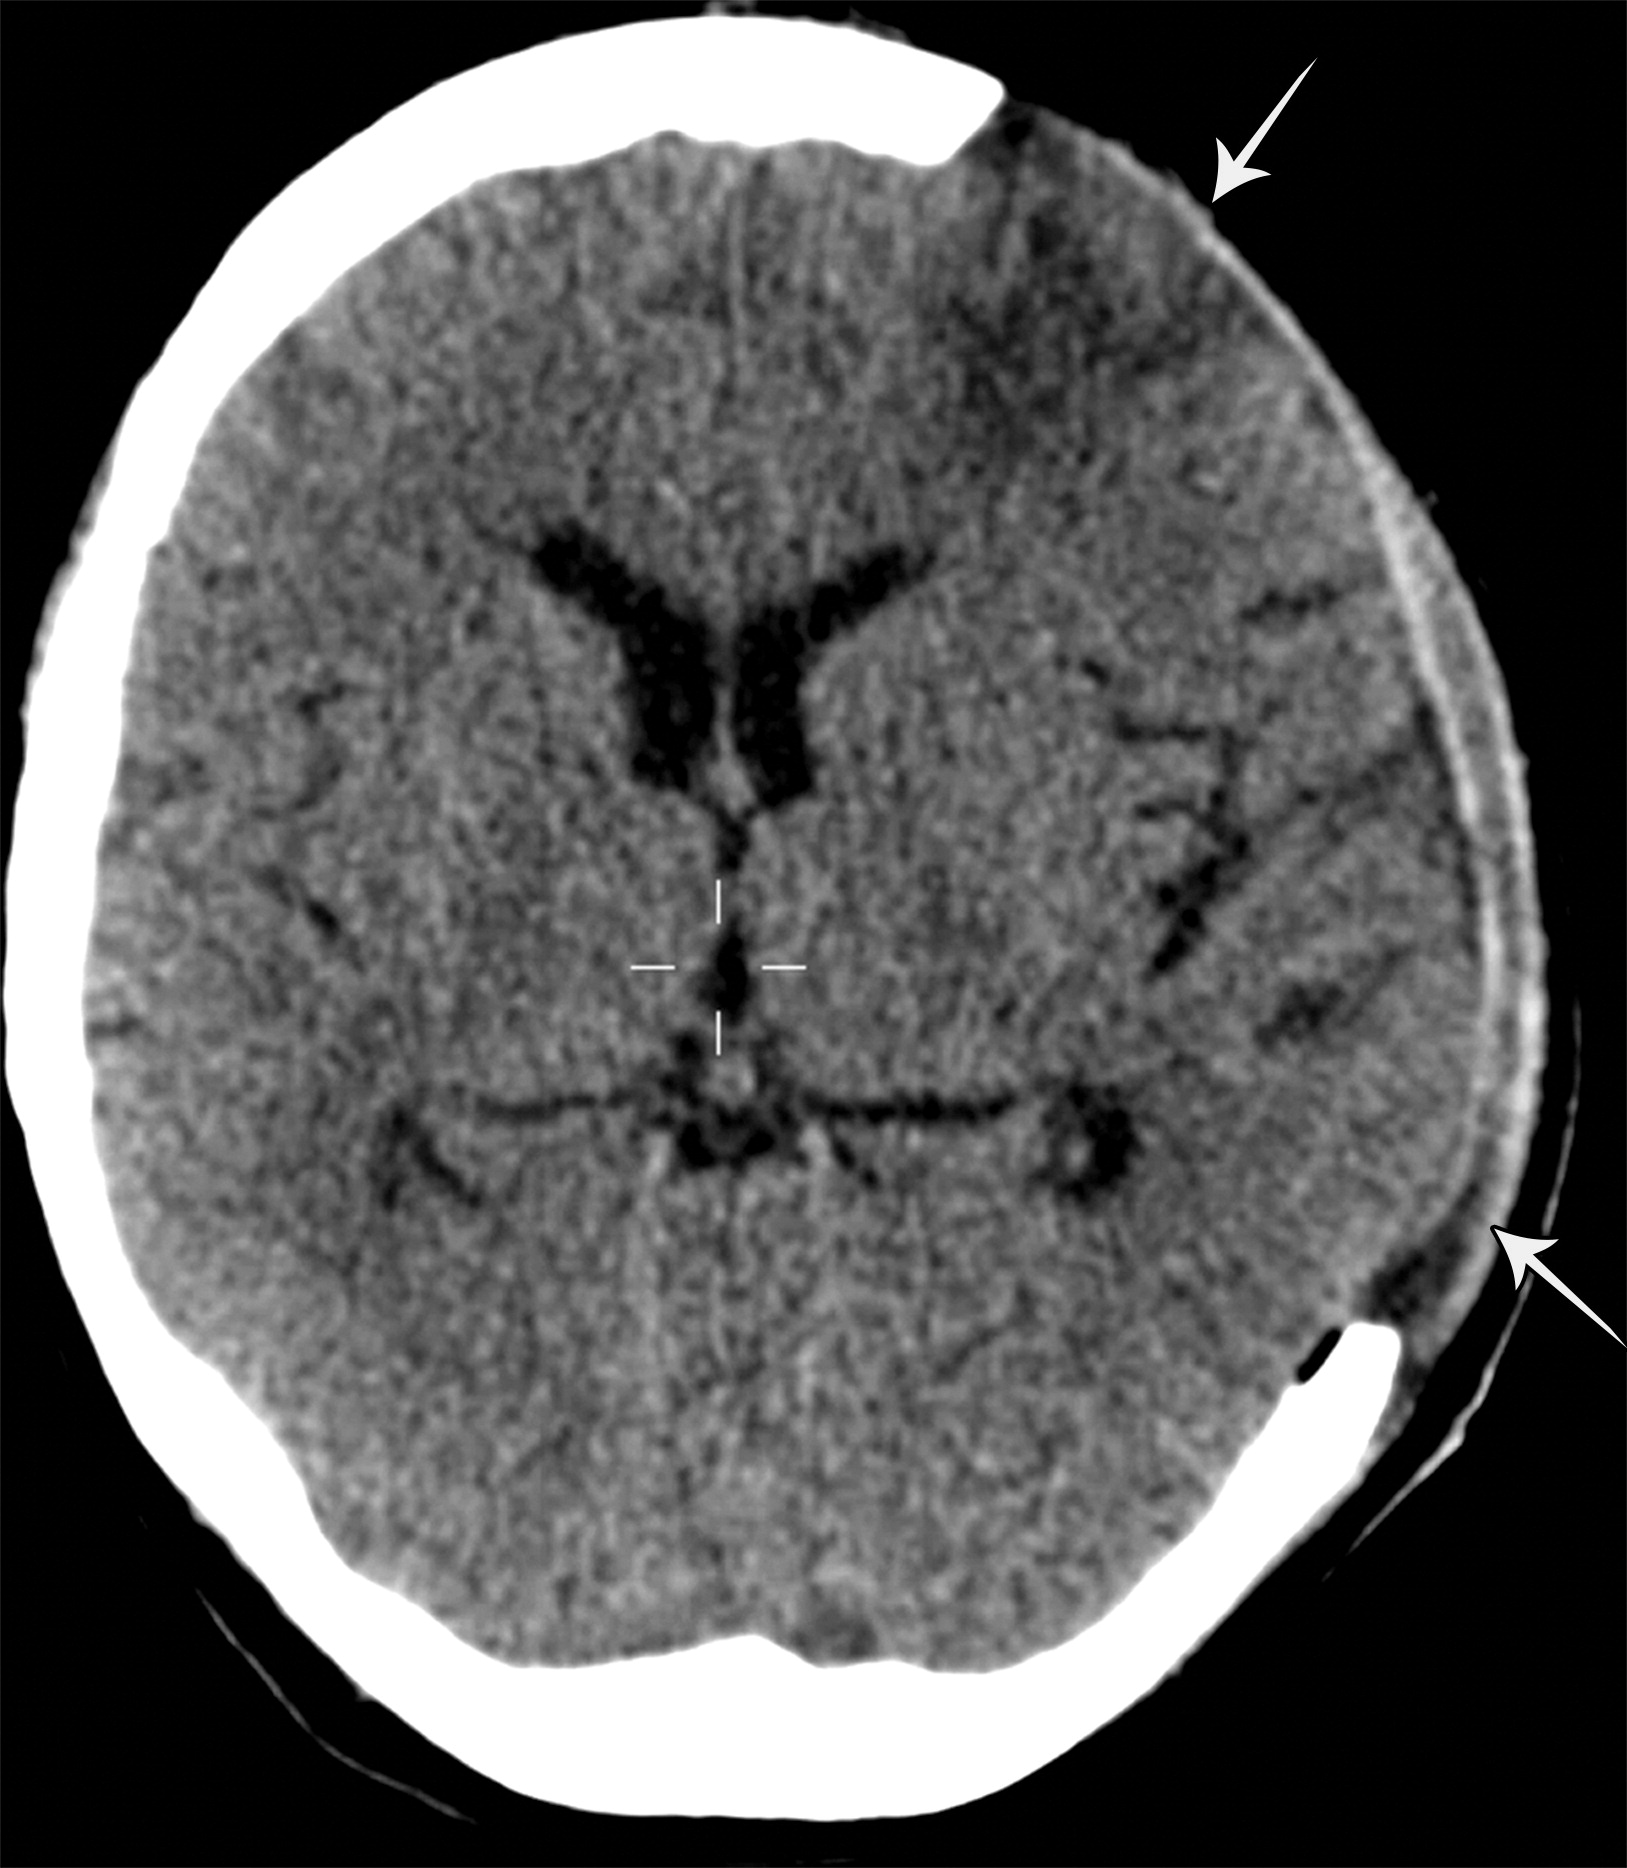

颅外脑疝。左侧额叶的急性梗死,注意右侧小灶状病变(白色短箭头)。数天后,患者出现血管源性脑水肿,并进行了去骨瓣减压术。

颅外脑疝。去骨瓣减压术后,脑实质从左侧额颞部缺损的位置疝出(白色长箭头)。大脑侧裂增大,左侧侧脑室的额角及枕角回缩。